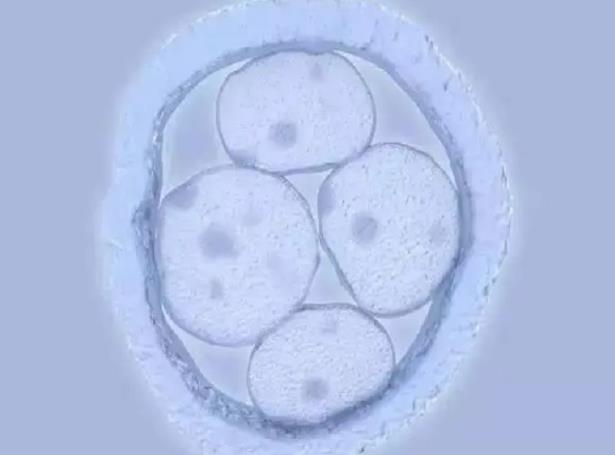

试管婴儿移植两个胚胎就一定能生双胎吗?你可能理解错了

揭秘试管移植双胎全过程!从胚胎培养到成功着床的关键步骤